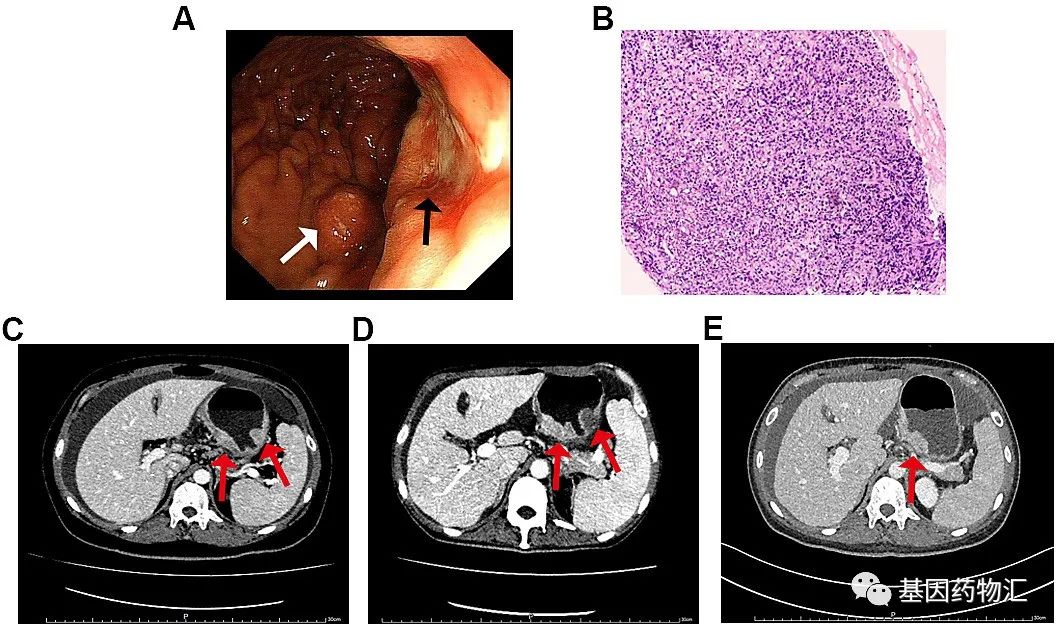

一位男性患者,51岁,2014年10月确诊腹部及后腹膜淋巴结转移性腺癌,基于免疫组化检查结果,原发部位首先考虑消化系统来源,胃系统来源可能性最大。

考虑到患者年龄较小,身体状况良好,肿瘤负荷较大,且较大可能性为转移性胃癌,因此选择了三药联合曲妥珠单抗的方案,即奥沙利铂+多西他赛+卡培他滨化疗方案与曲妥珠单抗靶向治疗联合。

患者首先完成了6个周期的治疗,腹部及腹膜后转移淋巴结明显减少。随后的治疗中,患者病情稳定无进展。

至2015年6月,患者复查时发现后腹部淋巴结明显增多,因此改用奥沙利铂+S-1(爱斯万)化疗方案联合曲妥珠单抗靶向治疗。治疗2个周期,患者耐受性较好,局部有复发,给予同步放化疗(胃微弯及腹膜后淋巴结放疗,与卡培他滨合用)。

但非常不幸的是,2015年12月患者复查CT时发现,肝右叶疑似出现了转移病灶。经过医生与患者家属的探讨,决定尝试阿帕替尼方案。

患者于2015年12月~2016年1月期间使用阿帕替尼靶向治疗,但治疗并没有效果。上腹部核磁共振检测结果显示,肝转移癌,共16个病灶,体积增大,且胃贲门旁淋巴结肿大。

为了更好地指导下一步的用药方案,患者接受了二代测序(NGS)。检测结果显示,患者MET基因扩增约4.1倍,ERCC基因扩增约2.2倍。随后,患者开始接受克唑替尼治疗。

用药2个月后,复查上腹部MR结果显示:患者肝脏未见明显转移瘤,胃贲门旁淋巴结较之前略微缩小,提示肝转移病灶完全缓解!

最终,患者得到了长达20个月的无进展生存期。